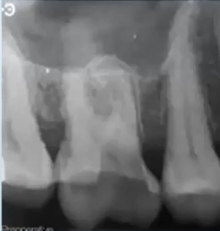

56yo pt had severe toothache for 4 weeks from upper right first molar which suddenly stopped

tooth was asymptomatic on the day he attended, he reported ‘part of the tooth came off recently’ whilst he was chewing

pt smokes 20/day and is a nocturnal bruxist

takes warfarin for atrial fibrilation

BPEs

2 2 2

FURTHER SPECIAL INVESTIGATIONS?

probing depth - perio disease, #

tooth sleuth - # cusps

test cavity - last resort if unsure on tooth’s vitality status

Large radiolucency – caries

Darkness, shadow that’s the decay/hole in your tooth, gone too far for us to save it as it have reached the nerves inside the tooth

Not sure if be able to restore it as since such a large proportion of it is decayed - empathy